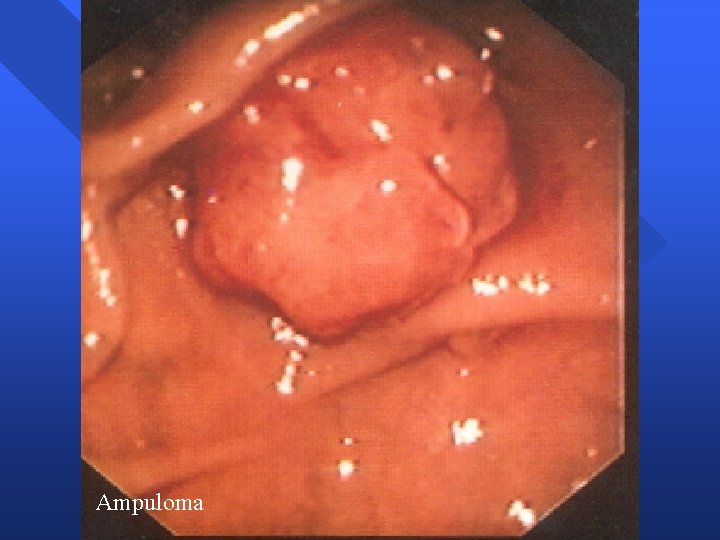

Tumores Ampolla Vater Ampuloma n Apariencia endoscópica – – – Papila mayor aumentada de tamaño Impronta suprapapilar colédoco distal dilatado Mucosa normal » Ampuloma intraductal – Mucosa neoplásica » Nodular, irregular, friable, ulcerada n Apariencia radiológica – Colédoco y conducto pancreático dilatados – Retraso evacuación drenaje – Estenosis distal / defecto repleción distal

Ampuloma